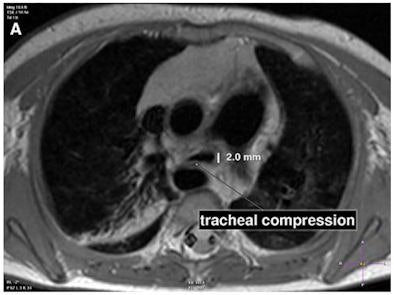

| This infant patient presented with tracheal stenosis due to a double aortic arch with an atretic left anterior part. Transverse turbo spin-echo images display the tracheal stenosis by the right aortic arch as seen in image A (top). A 3D volume-rendered reconstruction of the double aortic arch with the atretic left anterior arch is shown in image B (bottom). Each arch gives rise to the ipsilateral common carotid and subclavian artery. Images courtesy of Pediatric Cardiology. |